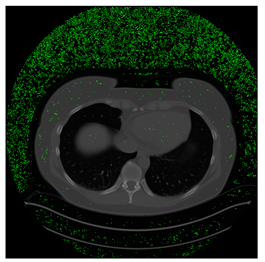

4.3. The Results

In this subsection, we describe three experiments used to measure the performance of the proposed method. The first experiment shows the stegoimage and marks the pixels’ positions that have been modified during the embedding process, as shown in Table 2, Table 3, Table 4, Table 5, Table 6 and Table 7. To make modified pixel positions have a pronounced effect, we set bpp (bit per pixel) rate at 0.05 and 0.025. It can be seen from the results that the proposed local complexity function can distinguish ROI and RONI from most of the medical images, so modified pixels are mainly gathered in RONI. However, it is observed that the proposed local complexity function cannot distinguish between ROI and RONI in the Prostate-MRI database due to the relative complexity of the image. Besides, “Modified BPP” represents the proportion of pixels in the image that have been modified. We observed that the performance of “baboon” in the grayscale standard images database is poor because that image’s pixels are relatively complex. It becomes challenging to select the more embeddable pixels based on the proposed local complexity function. Nevertheless, the modified pixel positions in other grayscale standard images, such as Lena and Barbara, are relatively smooth, verifying that our local complexity function is also applicable to general images.